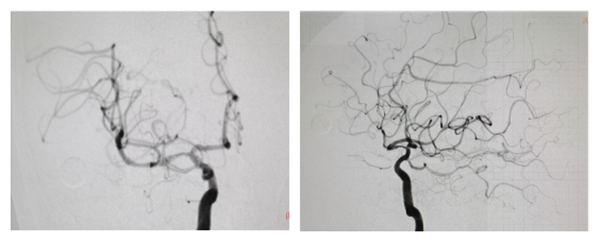

术后右侧大脑中动脉开通,远端血供恢复